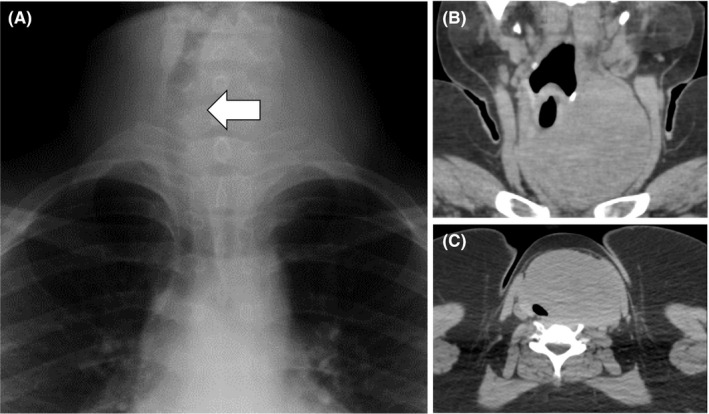

A 19‐year‐old girl who had a complaint of a swollen and enlarged feeling of her cervical mass for a few months visited our hospital (Figure 1). The patient had no particular past or family history including thyroidal disorders or other neoplasms. Cervical examination by ultrasonography revealed a diffusely enlarged left thyroid tumor showing a heterogenous pattern without clear capsule formation (Figure 2A), in which internal blood flow was augmented by a Doppler scan (Figure 2B). Endocrine examination showed that the patient was euthyroid and there were no thyroid autoantibodies (Table 1). A chest X‐ray showed a tracheal shift to the right and a dense shadow of the neck (Figure 3A). Computed tomography showed enlargement of the left thyroidal lesion and airway constriction (Figure 3B, coronal view; Figure 3C, horizontal view). Based on the results of cytology of a fine‐needle aspiration specimen, a follicular neoplasm was suspected. Left thyroidectomy was then performed, and a pathological diagnosis of follicular carcinoma (pT3N0M0 pStage I) was made on the basis of examination of the resected thyroid lesion (Figure 4). Cancer recurrence was not observed for a period of 1 year after surgery.

Figure 3.

A chest X‐ray showed a tracheal shift to the right and a high‐density area in her neck (A, arrow). Computed tomography showed an enlarged thyroid tumor shifting the trachea to the right (B) and constricting the airway (C)